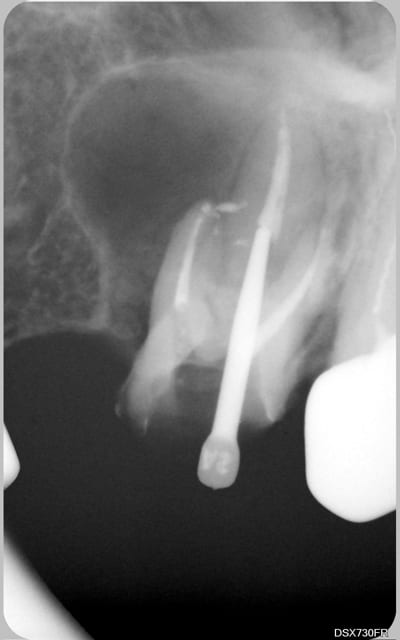

tu veux des images...en voilà 2...avant traitement et 6 mois plus tard...

C'est un beau début de cicatrisation.

Bel exemple du genre d'endo que je reprends au quotidien juste à coté de ta 7, lentulo fracturé et autres cochonneries.